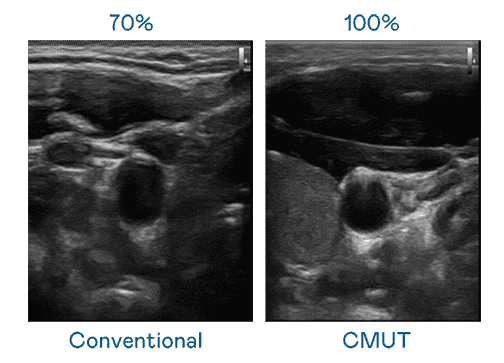

CMUT 技术是一种用电容式微机电元件来产生超音波讯号的技术。。与传统 PZT 压电式技术相比,,,CMUT 频宽增加 30%,,更宽频的超音波讯号让影像解析度大幅提升,,,,是实现高影像品质医疗超音波扫描、、促进精准医疗发展的关键技术。。。

大频宽带来超清晰影像

超音波影像的解析度高低,,,,首先取决于探头能发出的讯号频宽。。。。尊时凯龙 CMUT 可提供高清晰的超音波讯号,,,,提供高频宽、、高灵敏度、、影像纹理细节更高的超音波影像,,协助医护人员缩短影像判读时间及利用精准的医疗影像进行诊断。。。。